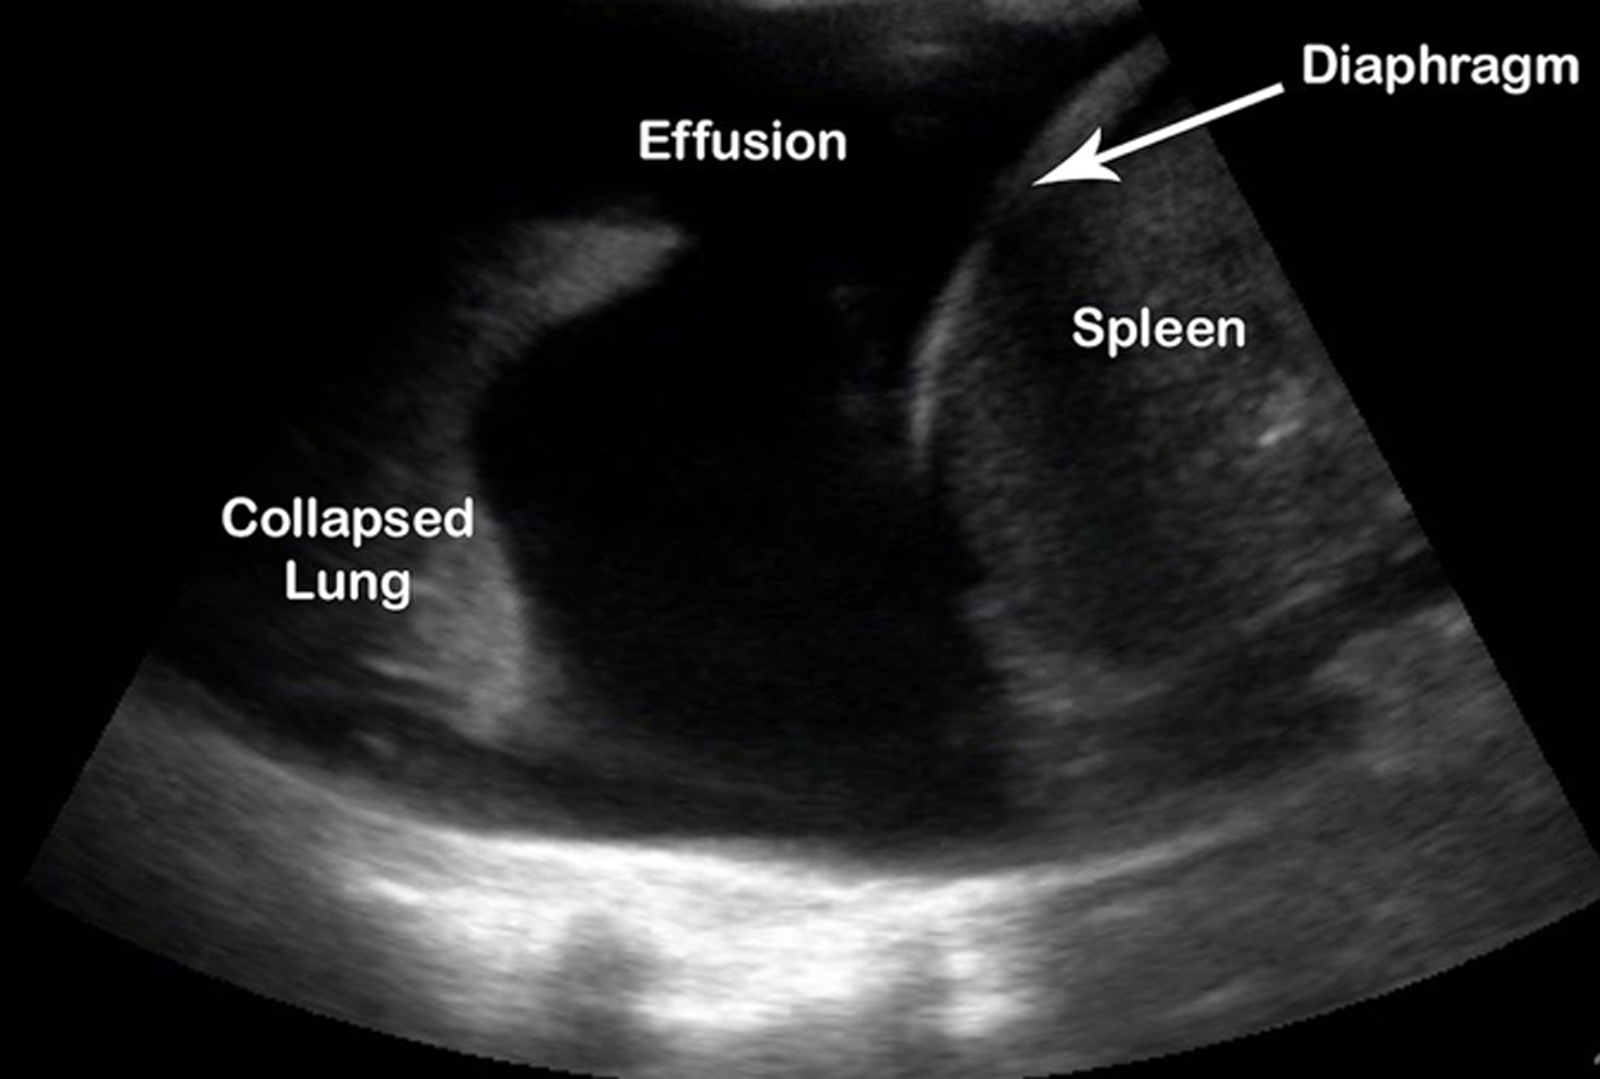

Pleural Effusion

An 84-year-old male with a history of atrial fibrillation and lung cancer who was examined via bronchoscopy 3 days before admission presents with acute onset shortness of breath. He is tachycardic, with a heart rate of 115 beats per minute, and hypoxic, with 95 percent oxygen on readmission. He has diminished breath sounds bilaterally and crackles on the left lung.

We see a large amount of anechoic material above the diaphragm consistent with a pleural effusion.

A pleural effusion is a pathologic accumulation of fluid in the pleural cavity and is classified by type: blood (hemothorax), serous (hydrothorax), chyle (chylothorax), or pus (pyothorax/empyema); and also classified by cause: exudative or transudative.

Lung point of care ultrasound is indicated when a patient presents with undifferentiated shortness of breath, hypoxia, and/or chest pain, or when abnormal breath sounds are noted on exam. Lung point of care ultrasound can also be used to differentiate between an effusion, infiltrate, and consolidation, as well as to safely guide procedures (thoracentesis).

The linear high-frequency probe is indicated when evaluating a patient for pneumothorax. However, the low-frequency transducer is optimal when evaluating for effusions. Furthermore, visualization of the effusion can allow you to estimate the size and evaluate the character to identify septations or other pathology that may indicate a complicated effusion.

Lung ultrasound has a higher diagnostic accuracy when identifying effusions as compared with X-ray. Sensitivity and specificity of lung ultrasound is 94 percent and 98 percent, respectively, as compared with X-ray, for which sensitivity and specificity is 51 percent and 91 percent (Yousefifard, et al). Small amounts (5 mL) may be seen, but minimum amounts of 20 mL or more are more reliably detected, with sensitivities reaching 100 percent with effusions more than 100 mL (Soni, et al).